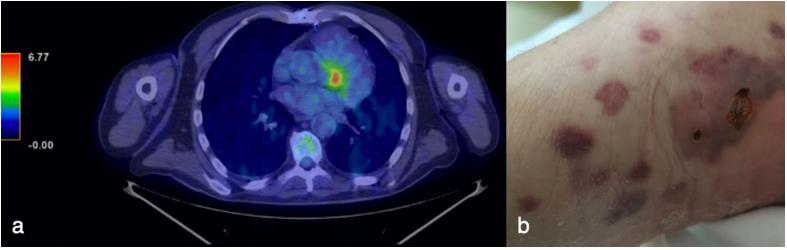

2021年6月,患者因一个多月的发热、体重减轻和疑似PVE就诊于传染科(图1)。经胸超声心动图(TTE)显示主动脉生物瓣膜上有活动赘生物,但经食管超声心动图未证实。住院期间,经胸超声心动图和经食管超声心动图重复检查,未确认PVE的诊断。然而,全身氟-18氟脱氧葡萄糖正电子发射断层扫描(18F-FDG PET)检测到示踪剂在主动脉生物假体附近积聚(图2a)。冠状动脉计算机断层造影和钆增强的心脏磁共振显示假体周围主动脉脓肿。全血计数显示贫血、血小板减少、白细胞减少和淋巴细胞减少,血液化学分析显示CRP和白细胞介素(IL)-6浓度升高,低蛋白血症和估计肾小球滤过率降低。

血培养及感染性心内膜炎筛查均为阴性。此外,还进行了非感染性心内膜炎的筛查(包括抗核、抗心磷脂、抗β2-糖蛋白1抗体和狼疮抗凝剂的检测),结果为阴性。尽管进行了多次抗生素治疗,但患者仍持续发热(图1),因此筛查了病毒感染(包括严重急性呼吸综合征冠状病毒2鼻咽拭子),血浆样本中仅人类疱疹病毒8(HHV8)的rtPCR低滴度阳性。患者没有淋巴结病、胸腔、心包或腹腔积液和肝肿大,有中度脾肿大和在住院第三天首次观察到的双脚紫色皮肤结节性病变(图2b)。对结节进行活检,HHV8的组织学分析和rtPCR均与KS一致(图1)。

图2. 心脏和皮肤检查结果。(a)2021年6月进行的全身氟-18-氟脱氧葡萄糖正电子发射断层扫描显示示踪剂在主动脉生物假体附近积聚。(b)患者右脚皮肤损伤,于2021年7月进行活检